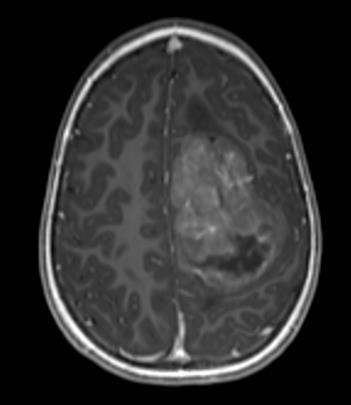

FIGUR 1: MR-bildene viser tydelig heterogenitet i hjernesvulster hos barn. A – Pilocytisk astrocytom i synsnerve (WHO grad ­1); B – Diffust astrocytom (WHO grad – 2); C – Høygradig gliom (WHO grad – 4); D – Diffust midtlinjegliom (WHO grad – 4); E ­ Dysembryoplastisk nevroepitelial tumor (WHO grad – 1); F – Gangliogliom (WHO grad – 1); G – Supratentorielt ependymom (WHO grad – 3); H – Pilocytisk astrocytom (WHO Grad – 1); I – Medulloblastom ( WHO grad – 4); J – Medulloblastom (WHO grad – 4); K – Ependymom ( WHO grad – 4); L ­ Glionevronaltumor forenlig med RGNT ( WHO – Grad 1). Alle pasienter har samtykket til bruk av bildene.